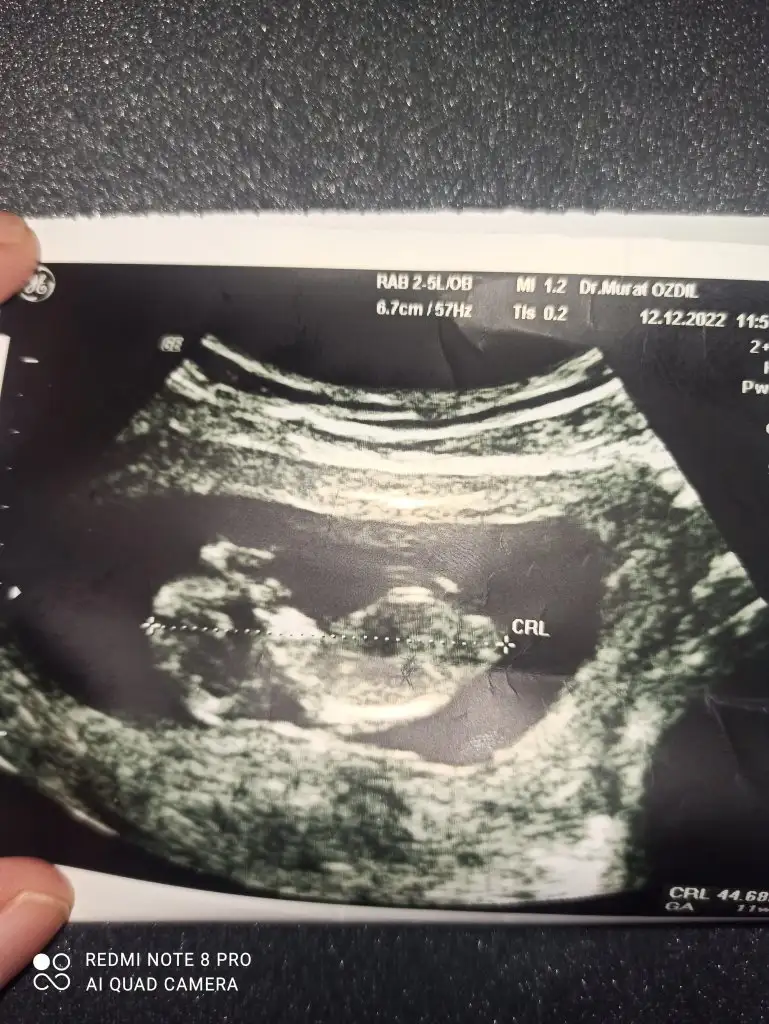

Amin canım cümlemizin sağlıklı sıhhatli olsun hayırlısıyla evlatlarımızı kulaklarımıza alalım. 12. Haftadayiz ama bebekler arasında 3 gün fark var buda çok önemli degil zamanla gelişimleri artiyormus. 12+1-12+4Maşallah canım ne güzel rabbim sağlıkla da kucağına almayı nasip etsin inş oğluşun ve kızınıbugün kaç haftalıktın öğrendiğinde?

Hamileliğiniz ilk nasıl hissettiniz ne gibi ağrı felan yaşadınız mı acabaAmin canım cümlemizin sağlıklı sıhhatli olsun hayırlısıyla evlatlarımızı kulaklarımıza alalım. 12. Haftadayiz ama bebekler arasında 3 gün fark var buda çok önemli degil zamanla gelişimleri artiyormus. 12+1-12+4

Amin canımAmin canım cümlemizin sağlıklı sıhhatli olsun hayırlısıyla evlatlarımızı kulaklarımıza alalım. 12. Haftadayiz ama bebekler arasında 3 gün fark var buda çok önemli degil zamanla gelişimleri artiyormus. 12+1-12+4